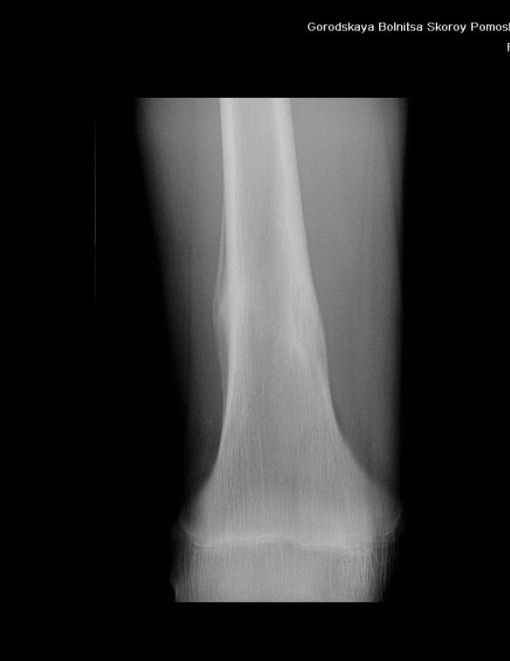

Здравствуйте, уважаемые коллеги!Представляю вашему вниманию интересный случай и пока что непонятный для меня в диагностическом плане. На днях в наше отделение (детской ортопедии и травматологии) поступил 13-летний мальчик по направлению из поликлиники с диагнозом: остеома нижней трети правого бедра.

Анамнез практически никакой: в следствие травмы (растяжение связок коленного сустава) от 07.11.2004 выполнены Rg-граммы в травмпункте и обнаружено опухолевидное образование. Первичные Rg-граммы я не публикую, так как они заметно худшего качества, да и динамики за прошедшие три недели не отражают. Болевой синдром купирован в течение трёх дней. В настоящий момент мальчика ничего не беспокоит. Ходьба не нарушена, опухоль пальпируется с трудом по задней поверхности в н\3 правого бедра, пальпация безболезненна, объем движений в суставах правой нижней конечности полный и симметричный. Кожа над опухолью не изменена.В нашей клинике проведено дополнительное обследование: общие анализы крови и мочи, биохимия крови без особенностей. Выполнены Rg-граммы на цифровом Siemens обычные и продольные томограммы срезами 3-5 мм, а также компьютерная томография поперечными срезами по 5 мм. Прошу обратить внимание, что на приведённых томограммах видны две полости 10х15 мм и 15х60 мм. Также имеются два опухолевидных образований наслаивающихся друг на друга: уплощённое и вытянутое 10х100 мм и элипсовидной формы 15х30 мм. Это хорошо заметно на фото a_1.jpg c_1.jpg и d_1.jpg. Плотность внутри полостей 125% от плотности костномозгового канала, плотность наружного опухолевидного образования 55% от плотности кортикального слоя. Также отмечается линия перелома по центру наружного опухолевидного образования.Исходя из полученных данных мнения в плане диагноза несколько разделились от 1)сочетания кортикальной фиброзной дисплазии и латентно протекавшего маршевого перелома н\3 правого бедра до 2)остеосаркомы. В отношении первого варианта не сходится отсутствие клиники при переломе такой крупной кости как бедро, второй вариант вообще оставлю без комментария, ибо некомпетентен. Хотелось бы услышать мнения коллег, с удовольствием ознакомлюсь с любыми предположениями и замечаниями.С уважением, Александр Е. КлоковОтделение детской ортопедии и травматологииБСМП г. Мурманска.

С облегчением спешу сообщить, что гистологический анализ подтвердил сложившееся интраоперационно мнение, что мы имеем дело с посттравматической перестройкой костной ткани (костной мозолью). Плюс к этому фиброзные кортикальные дефекты. В обшем, зла нет и слава Богу.